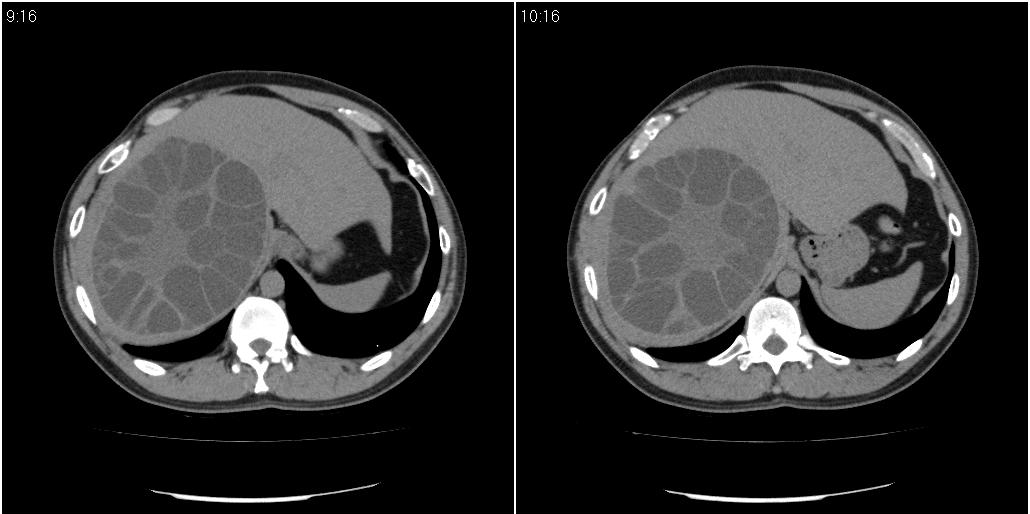

该患者70岁男性,手术后10年,现复查。2008年6月份本人曾经发过一极其类似的病例,只是部位略有差异。

多囊肝

肝脏多房性包虫囊肿

水上浮莲征,肝包虫囊肿。

肝脏及右侧胸腔包虫病。

大囊套小囊!肝脏多房性包虫囊肿